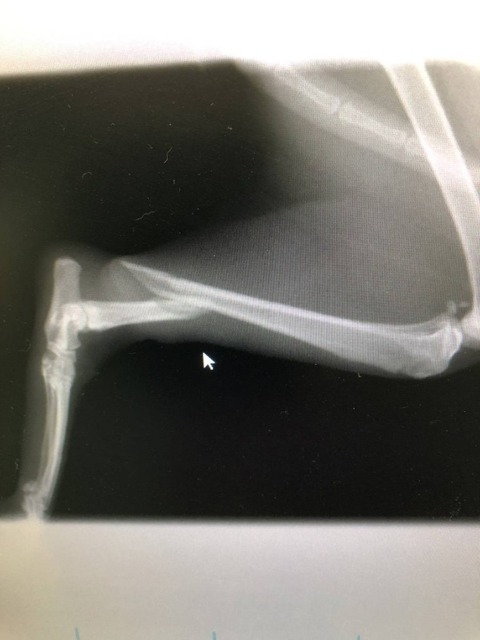

『大腿骨骨折だな』

・・・と偉そうに判断♪

大腿骨ではなく

脛骨の骨折でした。

えへっ・・・

早速

増田院長に

ピンニング手術をしてもらい

お昼すぎに

うちに戻って来ました。